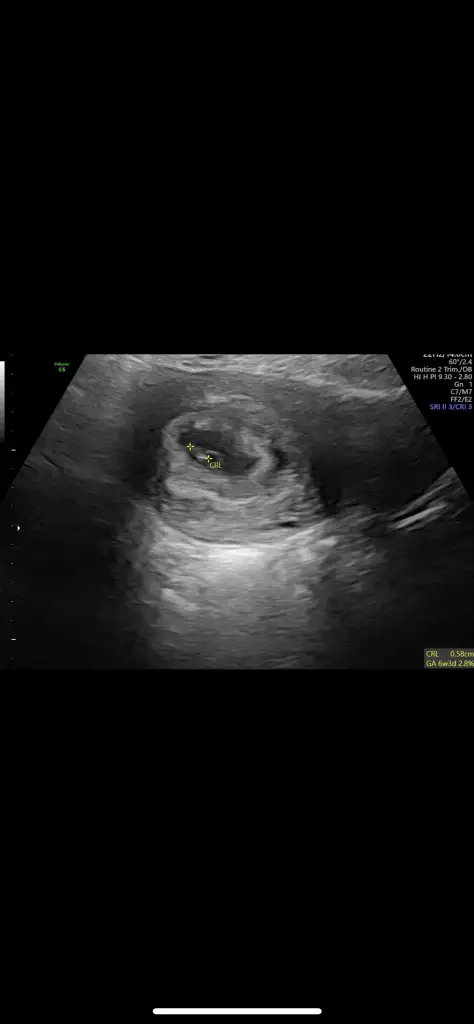

Kızlar bizde bugün doktora gittik. 10+4 haftalık olmuşuz İki hafta sonra ikili test için çağırdı Geçen gittiğimde hiç belli olmuyordu büyümüş bayağı Cinsiyet içinde 2 hafta sonra görürsem %60-%70 tahmin yapabilirim dedi